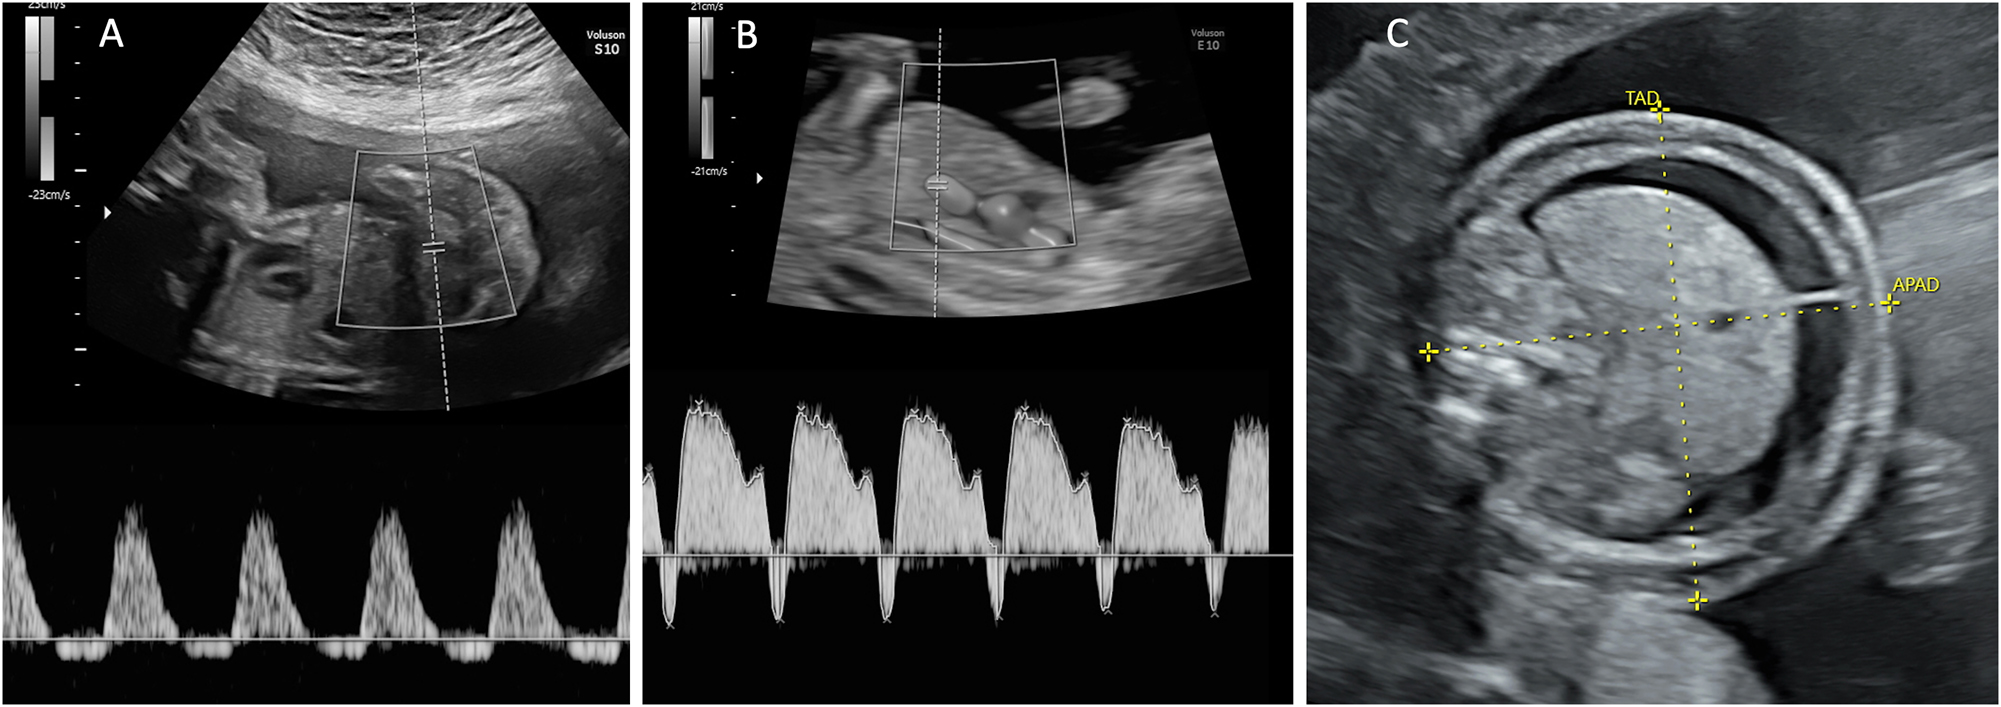

Beyond MCA-PSV measurements, several additional ultrasound findings may suggest TAPS, including differences in placental thickness and echogenicity. Typically, the donor’s placental share appears hyperechoic and thick, while the recipient’s portion presents hypoechoic and thin (Figure 5) [52]. Another characteristic finding is the ‘starry-sky liver’ appearance in the recipient twin, characterized by a hypoechoic liver parenchyma with hyperechoic portal venous walls (Figure 6) [53]. Similar to TTTS, TAPS can be classified into five stages of severity (Table 2) [50]. For early detection of TAPS, ultrasound examinations are recommended fortnightly beginning at 16 weeks’ gestation. Upon diagnosis of TAPS, weekly ultrasound monitoring is indicated [49].

Figure 5:

In TAPS, the donor’s placental share appears hyperechoic and thick, while the recipient’s placental share is hypoechoic and thin.

Figure 6:

Ultrasound appearance of the liver in twin-to-twin transfusion syndrome. (A) Abdomen of the polycythemic recipient twin showing hypoechoic liver parenchyma with hyperechoic portal venous walls, known as the ‘starry-sky’ liver appearance, and (B) the abdomen with the normal liver of the anemic donor twin.